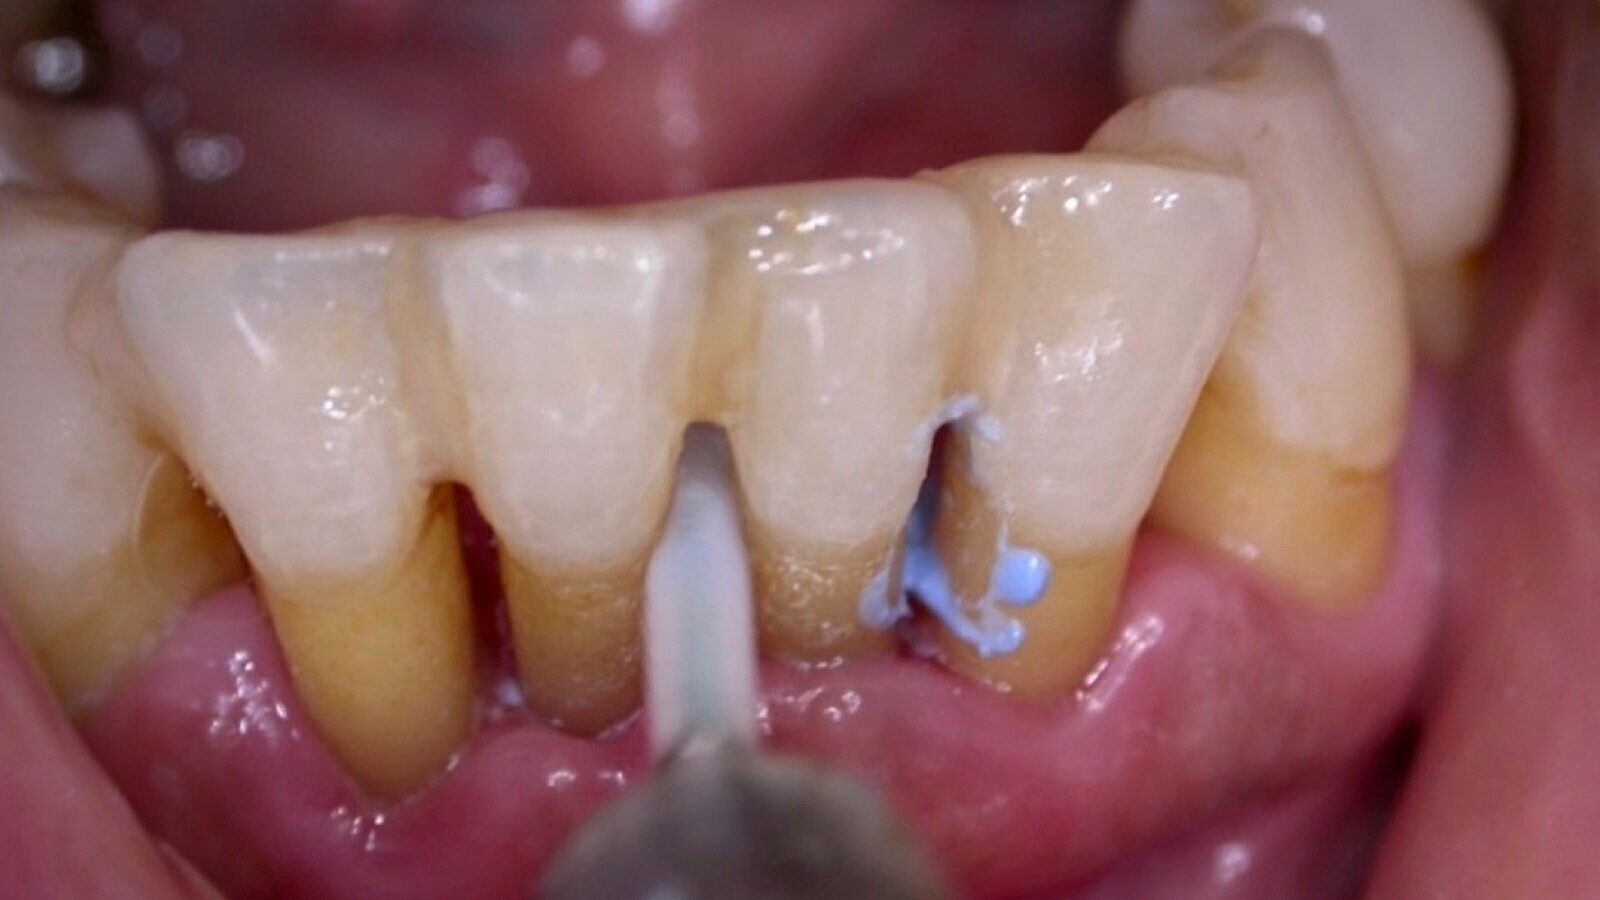

Figura 3. Paciente con riesgo moderado de caries, higiene deficiente, ausencia de dientes y obturaciones (historia de caries). En casos de riesgo moderado de caries se aconseja realizar revisiones cada 3 a 4 meses.